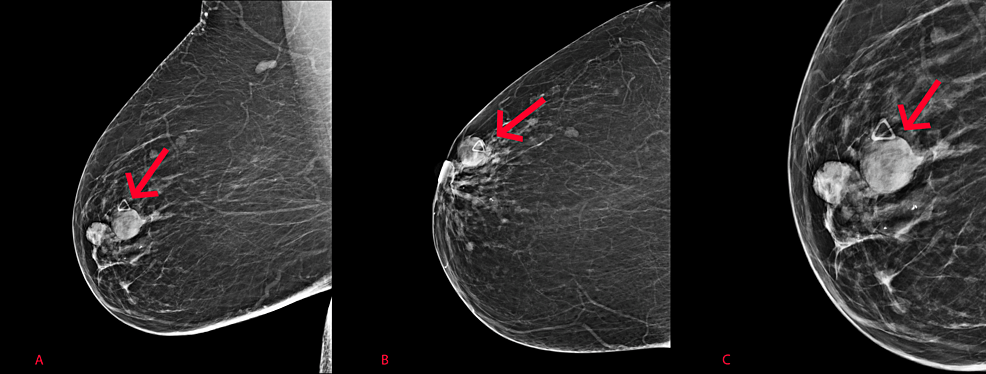

Диагностика папиллом молочной железы в Харькове

Перед началом лечения папиллом молочной железы маммолог анализирует жалобы пациентки и собирает анамнез. Диагностика внутрипротоковых папиллом включает:

- УЗИ молочных желез. Назначается для оценки структуры тканей, установления наличия, размера, вида и количества патологических образований в молочной железе, осмотра регионарных подмышечных лимфатических узлов.

При необходимости уточнения диагноза маммолог также может направить на МРТ молочных желез. Для определения природы опухоли назначается биопсия под контролем УЗИ. В зависимости от предполагаемого типа образования выполняются разные виды биопсии (трепан-биопсия или тонкоигольная аспирационная биопсия).